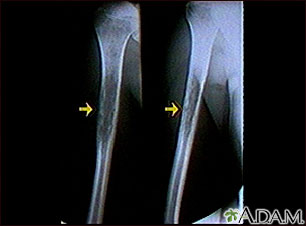

Ewings sarcoma - x-ray

This x-ray shows a malignant bone tumor (Ewing's sarcoma) of the upper arm bone (humerus). This type of tumor usually occurs during childhood and adolescence.